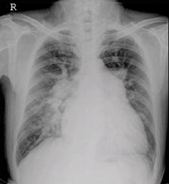

醫(yī)學(xué)影像學(xué)的發(fā)展經(jīng)歷了三個(gè)階段:X線的臨床應(yīng)用,放射學(xué)的形成,醫(yī)學(xué)影像學(xué)的形成。

總體走向是建立現(xiàn)代醫(yī)學(xué)影像學(xué):從大體形態(tài)學(xué)向分子、生理、功能代謝基因成像過渡;從膠片采集、顯示向數(shù)字采集電子傳輸發(fā)展;對(duì)比劑從一般性組織增強(qiáng)向組織疾病特異性增強(qiáng)發(fā)展;介入治療,以及與內(nèi)鏡、微創(chuàng)治療外科的融合、發(fā)展。

具體走向是:影像信息更加具有敏感性、直觀性、特異性、早期性;圖像分析由定性向定量發(fā)展:由顯示診斷信息向提供手術(shù)路徑方案發(fā)展;圖像采集與顯示:由二維模擬向三維全數(shù)字化發(fā)展;圖像存儲(chǔ)由膠片硬拷貝向軟拷貝無膠片化,乃至圖像傳輸網(wǎng)絡(luò)化發(fā)展;從單一圖像技術(shù)向綜合圖像技術(shù)發(fā)展。

從醫(yī)學(xué)影像學(xué)的角度講,其未來發(fā)展將集中四個(gè)特點(diǎn):①醫(yī)學(xué)影像技術(shù)的數(shù)字化;②醫(yī)學(xué)影像技術(shù)的網(wǎng)絡(luò)化;③醫(yī)學(xué)影像技術(shù)的融合化;④醫(yī)學(xué)影像技術(shù)的標(biāo)準(zhǔn)化。